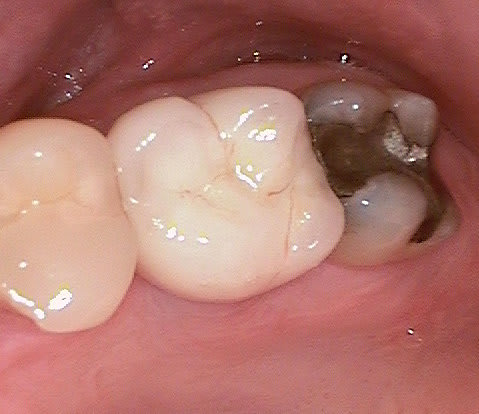

Un patient de 52 ans présente une fracture de racine au site 26.Après division de la racine, extraction de la dent,préparation de la cavité avec un foret conique triangulaire (3 faces,condensation de l´os), puis implantation à 50 Ncm (implant 10mm long, 4,5mm diamètre).Utilisation d´acide hyaluronique pour stimuler la synthèse des ostéoblastes.Pose d´un clip gingival pour préformer la gencive.Après 7 semaines, réalisation d´une empreinte fermée en 5 minutes.Une semaine après, fixation de la couronne définitive ( on observe déjà une ostéointégration).